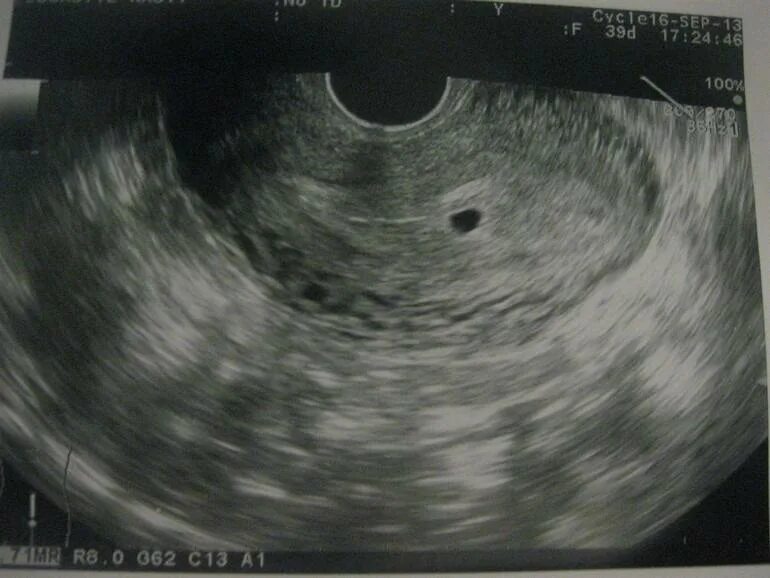

Как выглядит срока